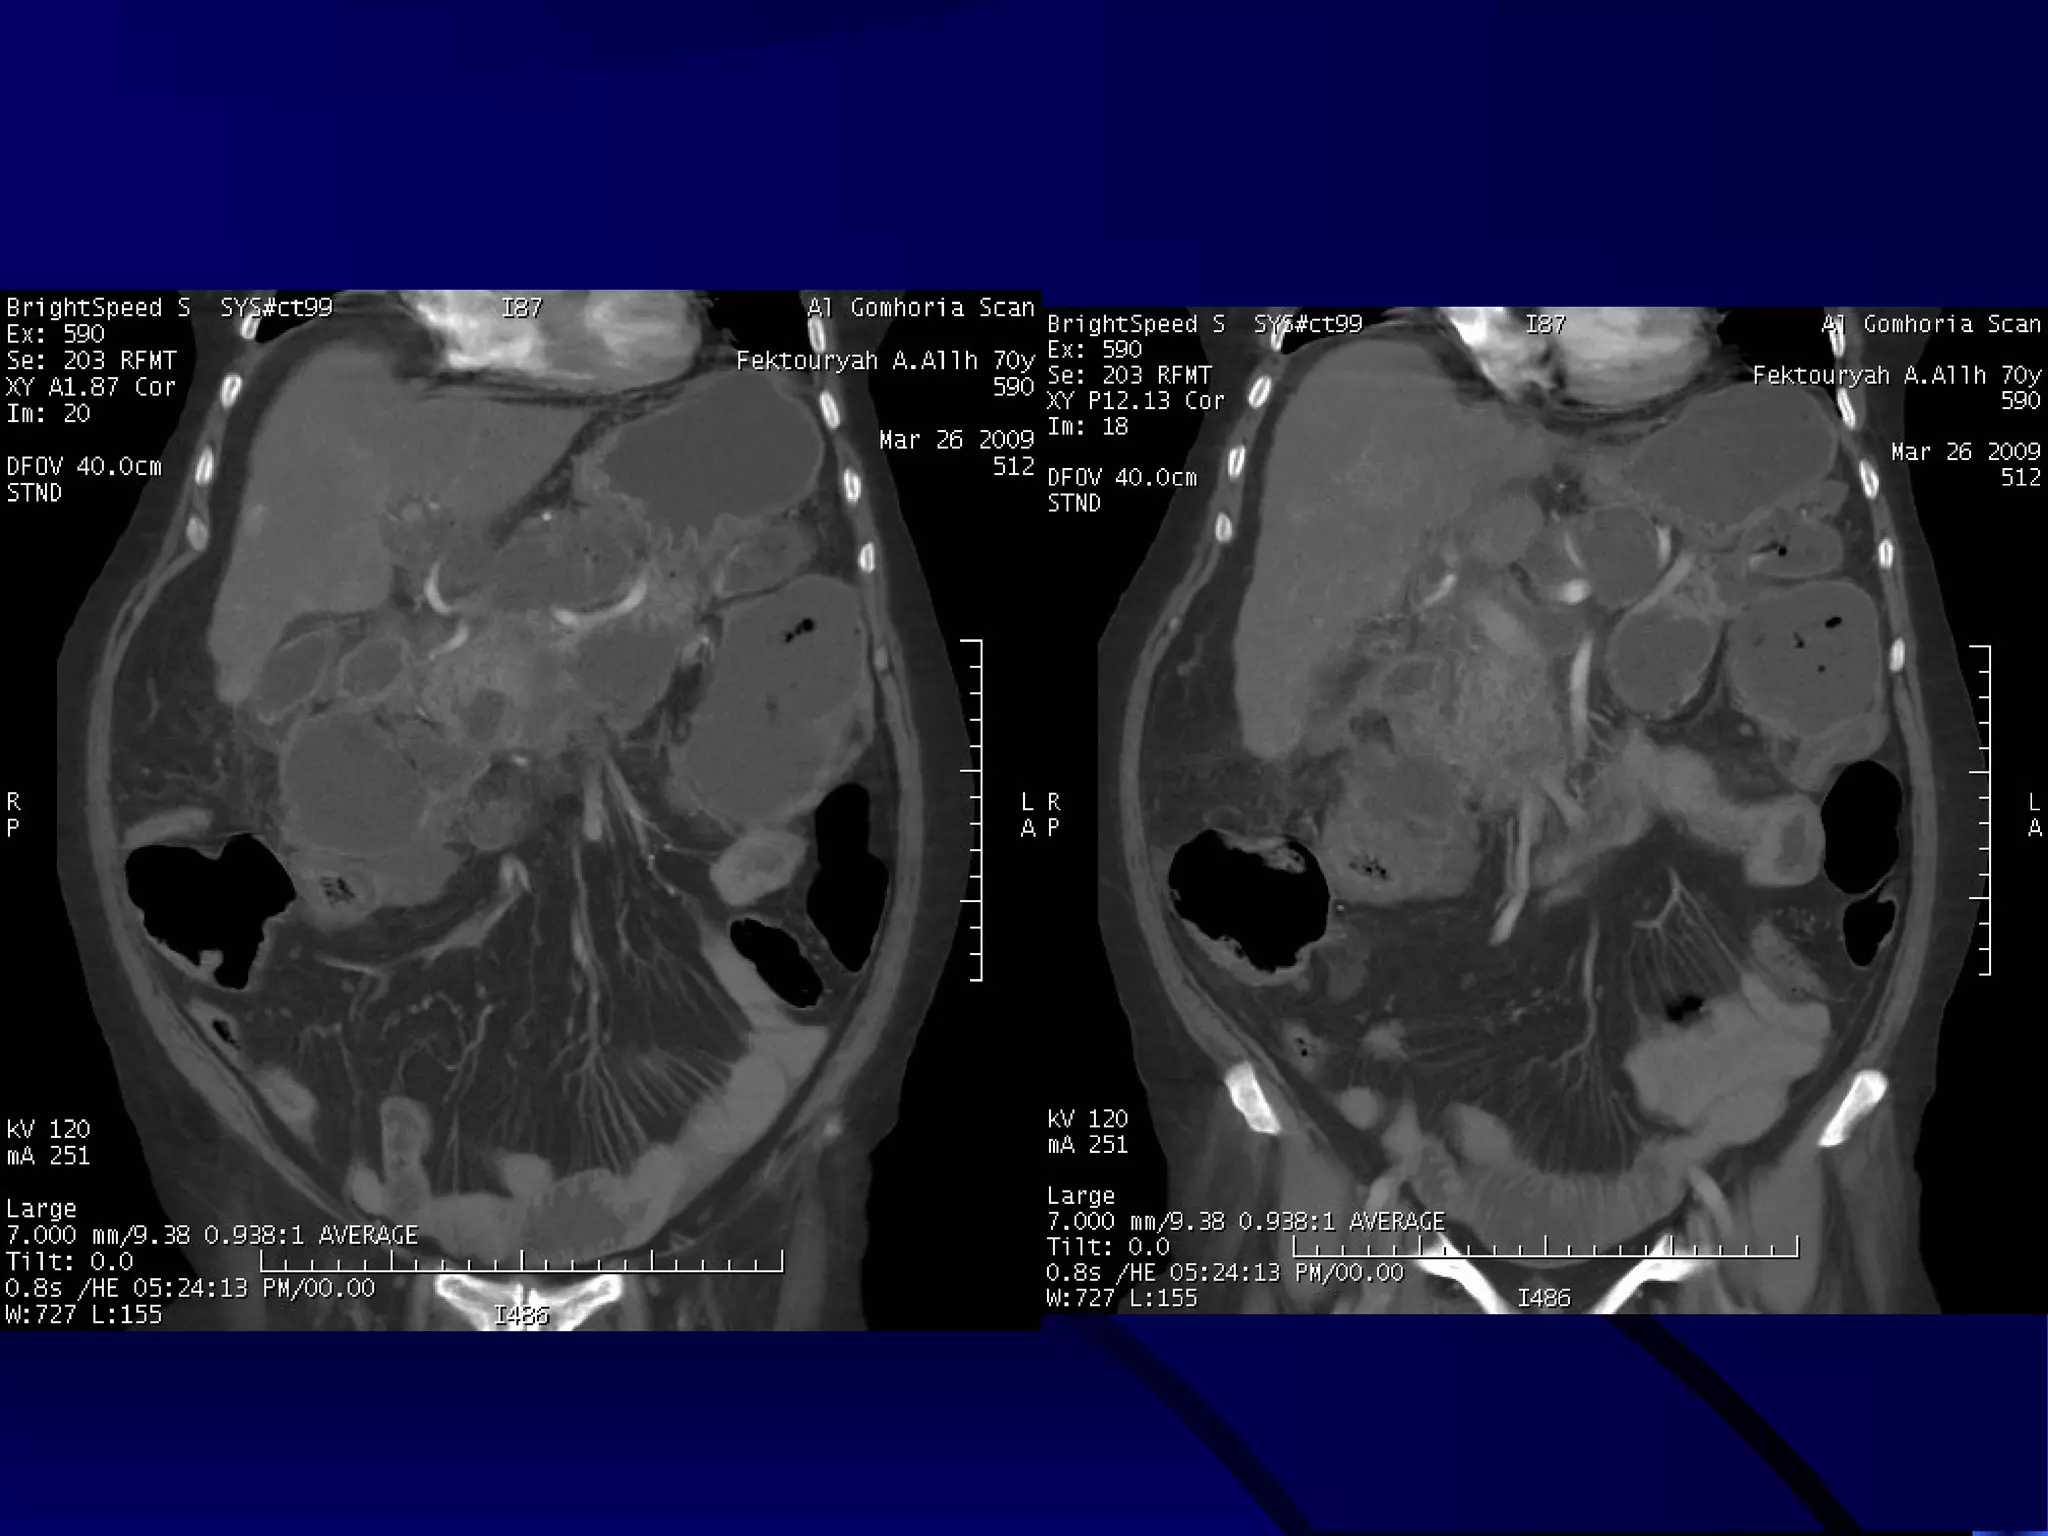

MALIGNANT LOWER POLAR LEFT RENAL MASS WITH

ENHANCING MALIGNANT THROMBUS WITHIN THE IVC

AND SECONDARY VARICOSITIES OF THE LEFT TESTICULAR VEIN.